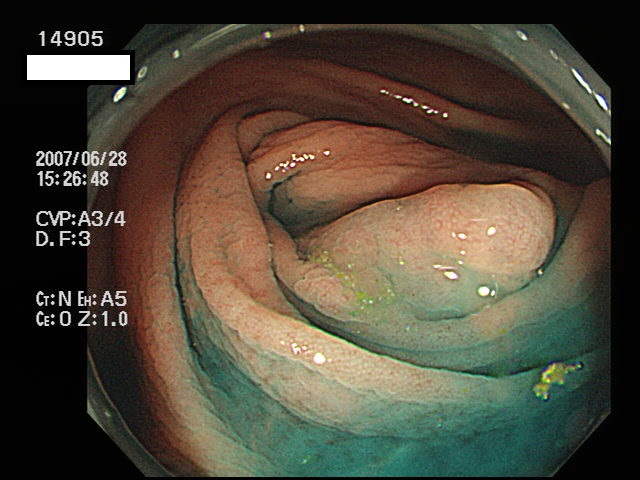

虫垂開口部の過形成ポリープ(SSAP)の例